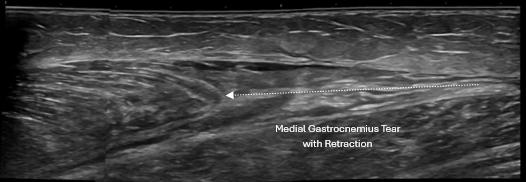

Ultrasound-guided procedures use real-time imaging to precisely visualize the target tissue while a procedure is being performed. This allows the physician to see exactly where the needle is placed, rather than relying on landmarks or feel alone.

This approach is especially important for tendons, ligaments, joints, and small or complex structures.

• Shoulder pain and rotator cuff pathology